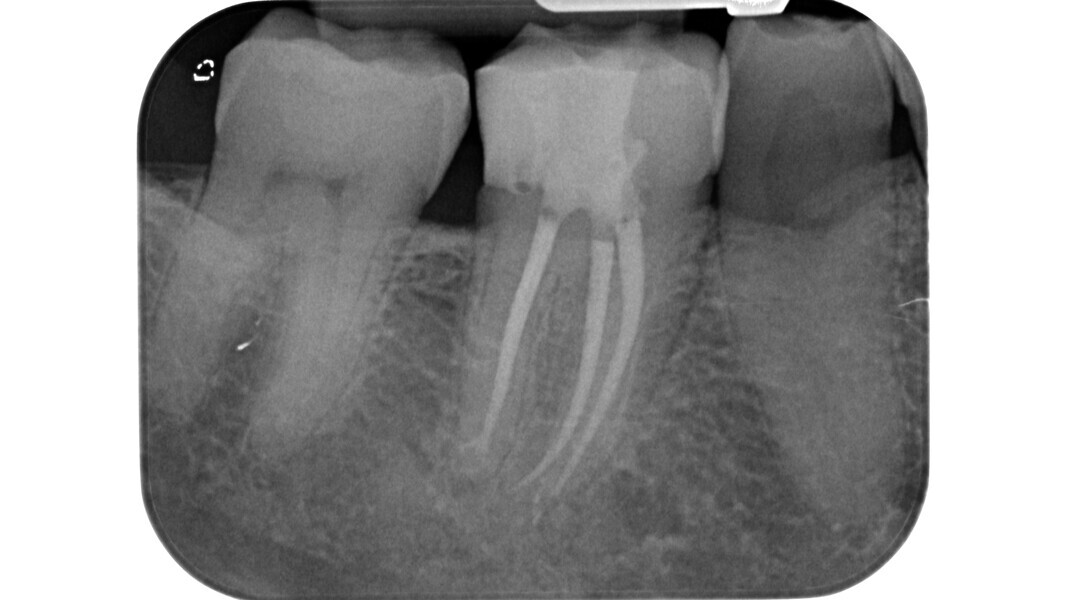

Fig. 1: Pre-op radiograph of a maxillary molar undergoing emergency treatment at another practice.

An inadequate access cavity in terms of position, depth and extension can lead to complications in the subsequent phases, making it impossible to locate the canal orifices, overstressing the mechanical nickel–titanium (NiTi) files or weakening the residual dental structure (Figs. 1–5). While, in the past, there was a tendency to emphasise the importance of a large access cavity that would allow the insertion of manual and mechanical instruments following the main axis of the canal, in recent years, the proposal of minimal access cavities defined in various ways (“ultra-conservative cavity”, “ninja cavity”, “truss access cavity”)4 has become predominant.